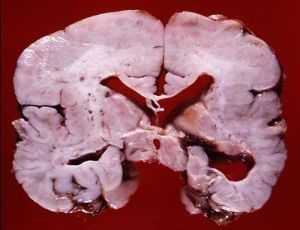

![пахигирия разрез мозга]()

Фото мозга в разрезе и на МРТ ребенка с диагнозом агирия

- Агирия (лиссэнцефалия) - аномалия формирования коры головного мозга, при которой извилины недоразвиты, слабо выражены, либо отсутствуют, архитектоника коры нарушена. Внешний вид головного мозга ребенка идентичен внешнему виду мозга плода на 3-4 месяце пренатального периода. Агирия является тяжелой формой лиссэнцефалии. Может быть как идиопатическим заболеванием, так и сопровождать другие патологии (синдром Миллера-Дикера, синдром Нормана-Робертса, синдром Уокера-Варбурга, врожденную мышечную дистрофию Фукуямы).

- Пахигирия является редкой аномалией развития центральной нервной системы, при которой в коре больших полушарий головного мозга формируется небольшое количество широких и плоских извилин. При пахигирии основные извилины укрупнены, а вторичные и третичные отсутствуют, борозды укорочены и выпрямлены, архитектоника церебральной коры нарушена. Данную патологию рассматривают как «неполную», более легкую форму лиссэнцефалии.